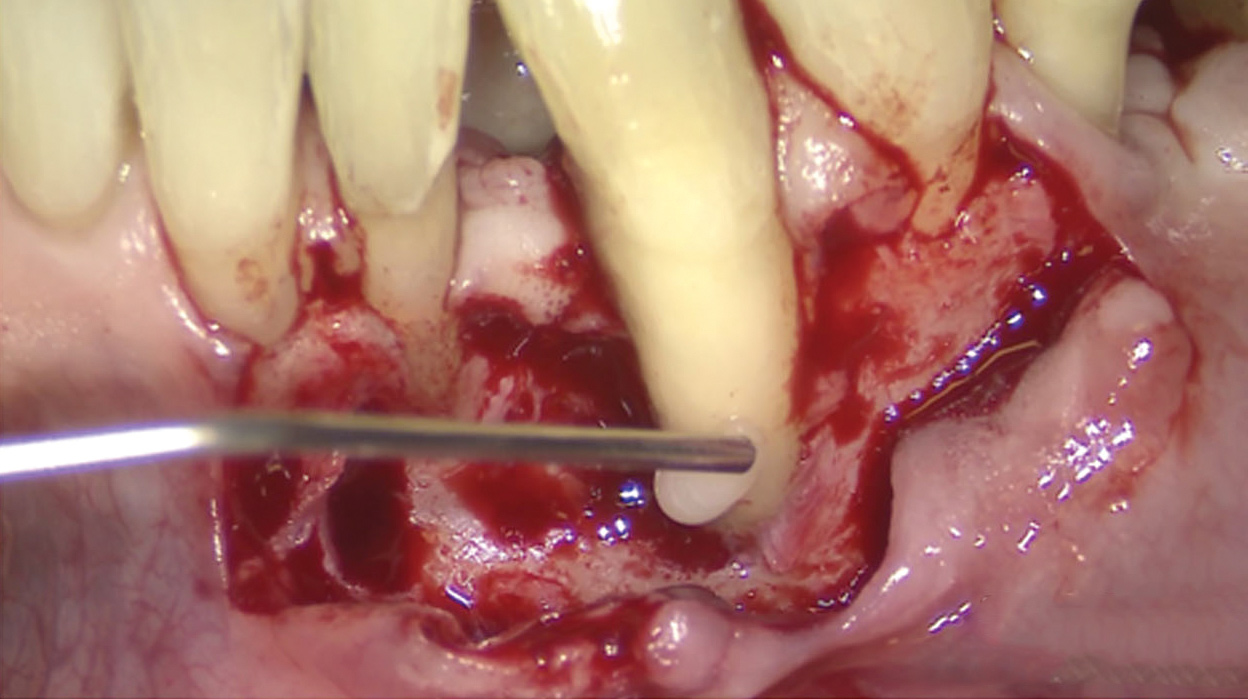

Fig 3. A 3D printed scaffold was designed using CAD software to fit a peri-osseous defect in a human patient. The scaffold consisted of a region with channels designed to support oriented PDL tissue formation and a region for the regeneration of osseous tissue. Fig 3: baseline;

Fig 4: defect model; Fig 5 through Fig 7: internal, tilted, and side views of scaffold, respectively; Fig 8 through Fig 10: coronal, middle, and apical

angles, respectively; Fig 11: cross-section diagram; Fig 12: labial scan image. (Images reprinted with permission from Rasperini G, Pilipchuk SP, Flanagan CL, et al. J Dent Res. 2015;94[9 suppl]:153S-157S.)

Fig 13. The scaffold was placed in the defect, where it remained for approximately 1 year. Fig 13: baseline; Fig 14: defect; Fig 15: scaffold matrix; Fig 16: scaffold placement; Fig 17: wound closure; Fig 18 through Fig 20: 2-month, 6-month, and 1-year postoperative, respectively. (Images reprinted with permission from Rasperini G, Pilipchuk SP, Flanagan CL, et al. J Dent Res. 2015;94[9 suppl]:153S-157S.)

Figure 13

Fig 14. The scaffold was placed in the defect, where it remained for approximately 1 year. Fig 13: baseline; Fig 14: defect; Fig 15: scaffold matrix; Fig 16: scaffold placement; Fig 17: wound closure; Fig 18 through Fig 20: 2-month, 6-month, and 1-year postoperative, respectively. (Images reprinted with permission from Rasperini G, Pilipchuk SP, Flanagan CL, et al. J Dent Res. 2015;94[9 suppl]:153S-157S.)